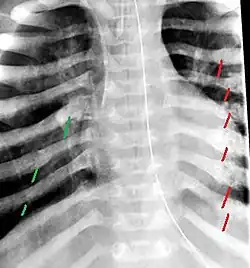

The material factual allegations of the amended complaint are as follows. Plaintiff was born on May 14, 1970. On repeated occasions during the first year of her life she was severely beaten by her mother and the latter's common law husband, one Reyes. On April 26, 1971, when the plaintiff was eleven months old, her mother took her to the San Jose Hospital for examination, diagnosis, and treatment. The attending physician was defendant Dr. Flood, acting on his own behalf and as agent of the defendant San Jose Hospital. At the time, the plaintiff was suffering from a comminuted spiral fracture of the right tibia and fibula, which gave the appearance of having been caused by a twisting force. Plaintiff's mother had no explanation for this injury. Plaintiff had bruises over her entire body. In addition, she had a non-depressed linear skull fracture which was then in the process of healing. Plaintiff demonstrated fear and apprehension when approached. Inasmuch as all plaintiff's injuries gave the appearance of having been intentionally inflicted by other persons, she exhibited the medical condition known as the battered child syndrome.

The complaint avers that as a proximate result of the foregoing negligence plaintiff was released from the San Jose Hospital without proper diagnosis and treatment of her battered child syndrome, and was returned to the custody of her mother and Reyes who resumed physically abusing her until she sustained traumatic blows to her right eye and back, puncture wounds over her left lower leg and across her back, severe bites on her face, and second and third degree burns on her left hand.

For example, the leading article by Kempe et al., op. cit., supra,[10] states that "A physician needs to have a high initial level of suspicion of the diagnosis of the battered-child syndrome in instances of subdural hematoma, multiple unexplained fractures at different stages of healing, failure to thrive, when soft tissue swelling or skin bruising are present, or in any other situation where the degree and type of injury is at variance with the history given regarding its occurrence . . . ." (Id., at p. 20.) Of the different types of fractures exhibited, an arm or leg fracture caused by a twisting force is particularly significant because "The extremities are the 'handles' for rough handling" of the child by adults. (Id., at p. 22.) The article also contains numerous recommendations to conduct a "radiologic examination of the entire skeleton" for the purpose of confirming the diagnosis, explaining that "To the informed physician, the bones tell a story the child is too young or too frightened to tell." (Id., at p. 18.) Finally, on the subject of management of the case it is repeatedly emphasized that the physician "should report possible willful trauma to the police department or any special children's protective service that operates in his community" (id., at p. 23) in order to forestall further injury to the child: "All too often, despite the apparent cooperativeness of the parents and their apparent desire to have the child with them, the child returns to his home only to be assaulted again and suffer permanent brain damage or death." (Id., at p. 24.)